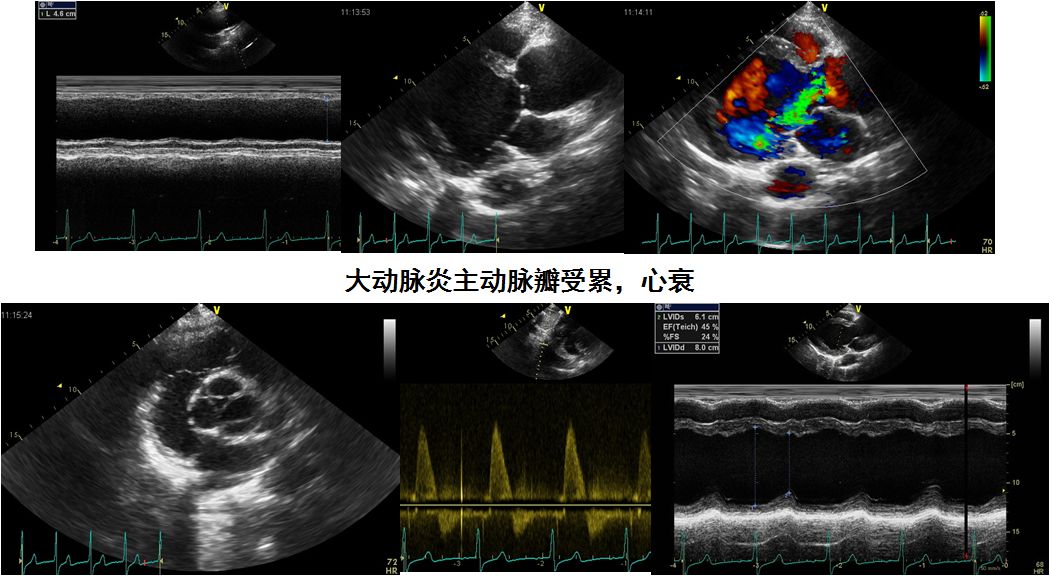

瓣膜(主动脉关闭不全多见)

瓣膜病(主动脉瓣多见)

白塞病的瓣膜病变主要表现为主动脉瓣关闭不全,可以急挂或慢性。

病理基础为主动瓣膜、瓣环及瓣环周围组织广泛的炎症,主动脉壁弹力纤维层损伤,中膜细胞浸润及外膜纤维化

也可累及二尖瓣、偶尔累及三尖瓣

未控制疾病活动而手术,术后缝线松解、瓣周漏、人工瓣膜脱落、吻合口假性动脉瘤及其它严重并发症的发生率达25%~40%

瓣膜脱垂,主动脉瓣关闭不全,主动脉窦扩张、主动脉扩张、夹层